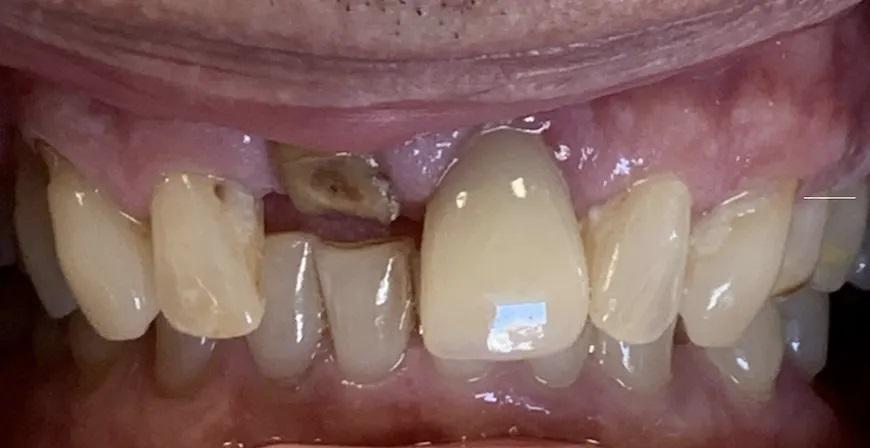

Пациент, мужчина 78 лет, обратился на консультацию по поводу перелома правого верхнего центрального резца (зуб 1.1) (Фото 1). Он пользовался временным частичным протезом для замещения коронки зуба. Пациент выразил желание заменить зуб имплантатом. При изучении анамнеза значимых соматических заболеваний не выявлено.

Фото 1. Пациент обратился с переломом правого верхнего центрального резца (зуб 1.1) на уровне десны.